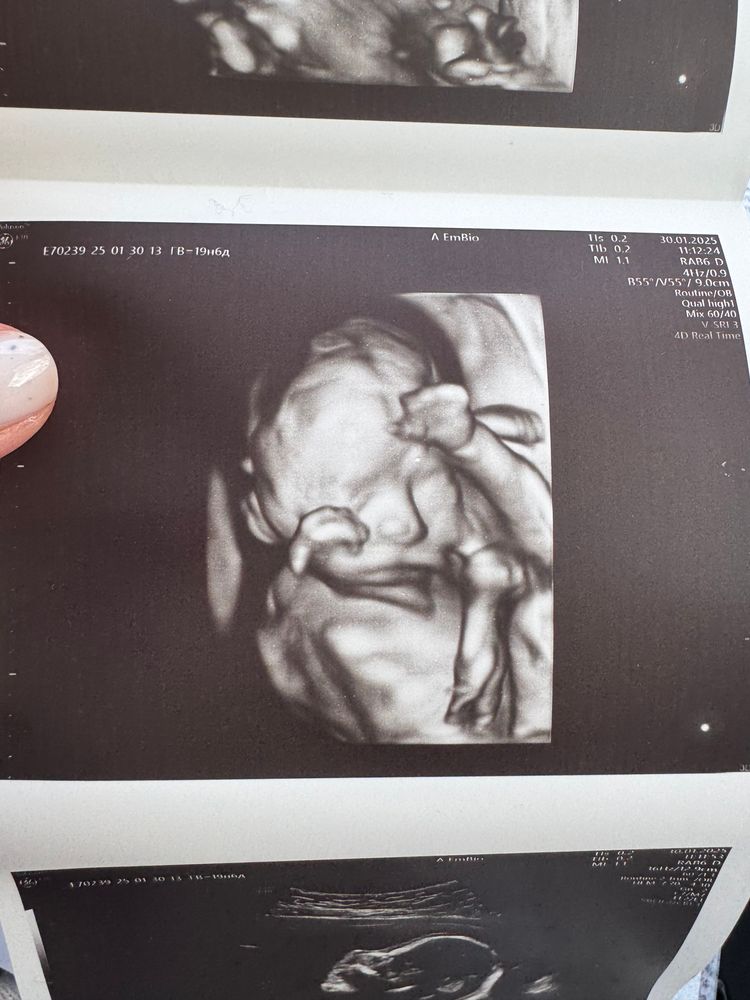

Пятничные замеры, 21 неделя и 2й скрининг

Что со вторым скринингом. У нас устроено так, что Г открывает направление, а записывает сама Жк, просто ставит перед фактом, что такого-то числа во столько-то у вас скрининг. Ок. 19 недель. Тишина. Я позвонила, меня заверили, что все ок, ждите, запишем:) 20 недель. Тишина. А ещё у меня было открыто направление на анализ мочи, пошла в жк за стаканчиками халявными и с оказией подошла на ресеп. Говорю, мол, а че со скринингом то, дамы? В четверг у меня 21 неделя. Они пошли узнавать и как давай бегать) Никто и не собирался меня никуда записывать😅 Они просто убрали куда-то мою карту и на этом всё. Перепугались, бегают, бегают. А все на неделю уже расписано. Мне смешно, но стою молчу. Я прошла скрининг платно. А если бы не прошла??? Вот бы 4.02 все так удивились, когда узнали бы, что все просрали. Нашли окно на сегодня:) Бонусом со страху записали на 25 февраля на гтт.

Съездила, посмотрела Агушу, все окей. За 2 недели набрала 200г примерно. Сейчас предполагаемый вес 400г. Доктор спросила знаю ли пол, хочу ли знать) подтвердили Агату:) Котик ну вылитая сестра:)) Муж говорит а если они одинаковые будут 😅 Ну, значит будут:))